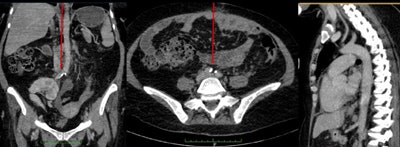

The correlation between ancient and modern Egyptians in the number of vascular beds involved with atherosclerosis was "striking," the study authors wrote. The disease tended to begin in the aortoiliac beds almost a decade earlier than in the coronary and carotid beds.

In both ancient and modern populations, "vascular calcification starts at the peripheral vascular bed (iliofemoral then aortic beds), then spreads to the target vessels (coronary and carotid beds) around a decade later than the onset of aortoiliac calcification," the authors wrote. There was also a trend toward higher incidence of vascular calcification among female mummies, but not modern Egyptians. Allam and colleagues hypothesized that the women may have been exposed to household smoke.

In a previous analysis of large numbers of modern patients (the Multi-Ethnic Study of Atherosclerosis, or MESA), abdominal aortic calcification was shown to be strongly associated with subclinical cardiovascular disease in other vascular beds, including the coronary, carotid, and leg arteries, the authors noted. This led investigators to conclude that the high prevalence of abdominal aortic calcification, even when coronary or carotid disease was not present, might suggest that atherosclerosis began earlier in the abdominal aorta compared to event-related vascular beds such as the coronary arteries.

And if disease begins in the abdomen before it reaches the coronaries, maybe that's where screening should start, according to Allam. "Occurrence of aortoiliac calcification a few years earlier than the coronary arteries could be used as an important screening tool for effective preventive cardiology strategies," he wrote in his email.